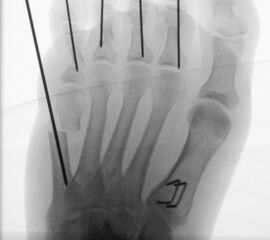

=> Risikoabwägung der radiologisch leicht erhöhten Strahlenbelastung intraoperativ

In der minimalinvasiven Fußchirurgie ist es unabdingbar, die Fräse in ihrer Position zum Knochen radiologisch zu kontrollieren, damit vulnerable Wachstumsfugen oder angrenzende Gelenke nicht verletzt werden. Zu diesem Zweck werden mit einem Bildwandler während der Operation die genaue Position der Fräse und der Osteotomieverlauf überprüft, was die Strahlenbelastung im Vergleich zu offenen Verfahren erhöht. Diese Strahlenbelastung hat potenziell einen schädigenden Einfluss auf den noch blutbildenden Knochen von Heranwachsenden. Gesicherte Landmarken am Fuß können die notwendige Zahl der Röntgenbilder und damit die Strahlung minimieren. Ist es erforderlich, mehrere Knochen zu osteotomieren, wie zum Beispiel im Bereich der Kleinzehen, werden anhand der Landmarken kleine Injektionsnadeln auf Höhe der geplanten Osteotomien vorgelegt und radiologisch im Bildwandler (BV) dokumentiert (Abb. 11). Ein solches Bild schafft eine gute Orientierung, sodass auf radiologische Kontrollen intraoperativ weitestgehend verzichtet werden kann.

Abb. 11: Lokalisation mehrerer Stichinzisionen mit einem Röntgenbild.

Zum Lesen der Bildbeschreibung und zur Vollansicht bitte das Bild anklicken. Bild: A. Helmers.